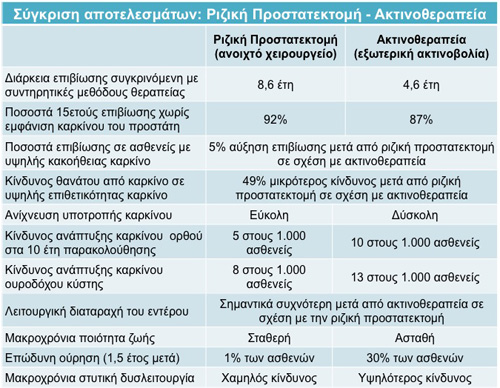

Οι παρακάτω πίνακες συγκρίνουν τ’ αποτελέσματα θεραπειών καρκίνου του προστάτη και ειδικότερα αντιπαραθέτοντας το χειρουργείο (ριζική προστατεκτομή), που θεωρείται ο χρυσός κανόνας για την θεραπεία του εντοπισμένου καρκίνου του προστάτη, με την ακτινοθεραπεία (θεωρούμενη σαν βραχυθεραπεία και σαν εξωτερική ακτινοβολία). Τα δεδομένα αφορούν την επιβίωση, την υποτροπή του καρκίνου, την συχνότητα εμφάνισης καρκίνου του ορθού και της ουροδόχου κύστης, την λειτουργία του εντέρου, την λειτουργία της ουροδόχου κύστης και της στύσης.

Σ’ αυτόν το πίνακα η ριζική προστατεκτομή περιλαμβάνει όλα τα είδη των ριζικών επεμβάσεων στον προστάτη (ανοιχτό χειρουργείο μέσω μίας μεγάλης τομής στην κοιλιά, συμβατική λαπαροσκοπική ριζική προστατεκτομή καθώς και da Vinci προστατεκτομή). Όπως μπορείτε να διαπιστώσετε το χειρουργείο προσφέρει μετρήσιμα σημαντικά περισσότερα προτερήματα συγκριτικά με την ακτινοβολία όσον αφορά την τα αποτελέσματα και την επιβίωση.

Βιβλιογραφικές αναφορές για τον Πίνακα αυτόν θα βρείτε κάνοντας κλικ ΕΔΩ.